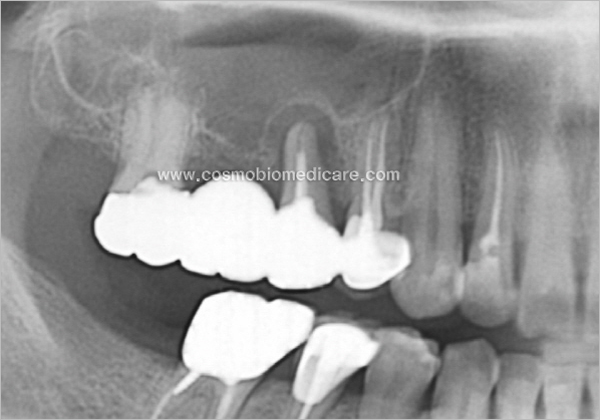

Clinical Cases

• Case2